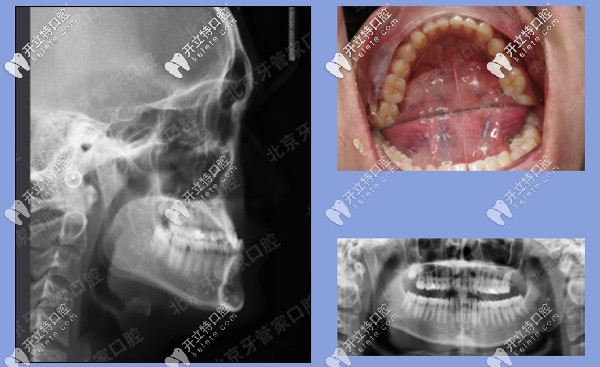

前期檢查:反合(又稱地包天),骨性三類,磨牙關(guān)系三類。下前牙已經(jīng)發(fā)生舌傾,存在縫隙。

患者牙齒前期檢查

治療方案:內(nèi)收下牙列,上頜唇傾前牙,代償性掩飾治療。

矯治器:金屬固定矯正